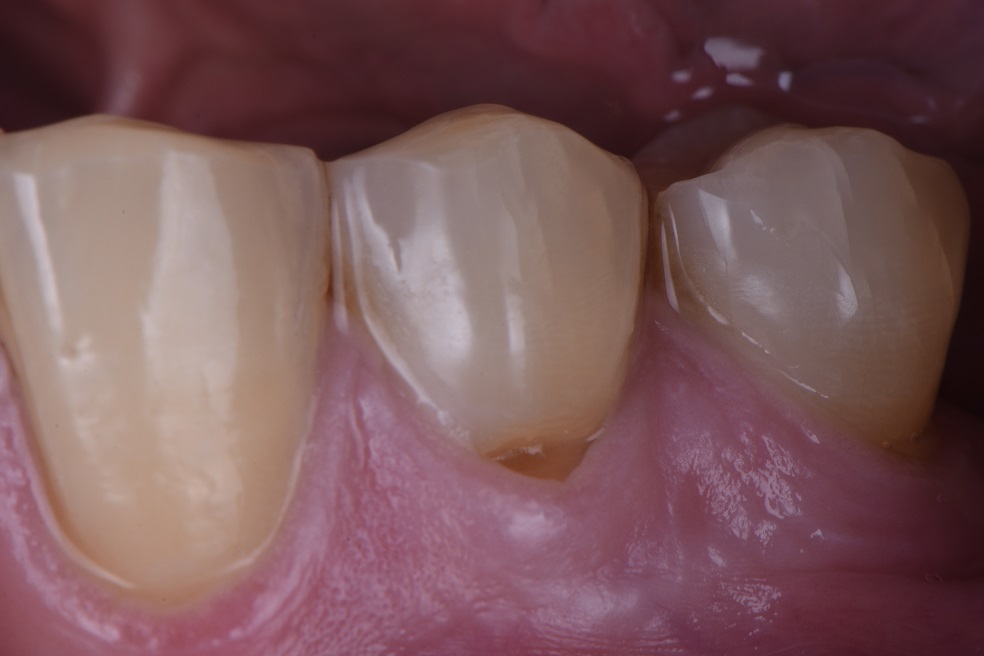

Root abrasion lesions from toothbrushing What Is Gum Abrasion toothbrush abrasion is a type of tooth wear caused by brushing too hard, too long or with the wrong technique. learn how to identify and treat a cut on the gums at home or when to seek medical care. Find out the common causes,. tooth abrasion is a dental issue that can cause permanent damage to your. What Is Gum Abrasion.

Root abrasion lesions restored and protected What Is Gum Abrasion learn how to identify and treat a cut on the gums at home or when to seek medical care. tooth abrasion is a dental issue that can cause permanent damage to your teeth if left untreated. dental abrasion is the wearing away of tooth enamel that can cause sensitivity,. dental abrasion is a condition that occurs. What Is Gum Abrasion.

Cervical Abrasion Lesions Under the Gum Cervical Abrasion Lesions Under What Is Gum Abrasion abfraction is the loss of dental matter around the gumline caused by physical forces on the tooth. dental abrasion is the wearing away of tooth enamel that can cause sensitivity,. tooth abrasion is a dental issue that can cause permanent damage to your teeth if left untreated. toothbrush abrasion is a type of tooth wear caused. What Is Gum Abrasion.